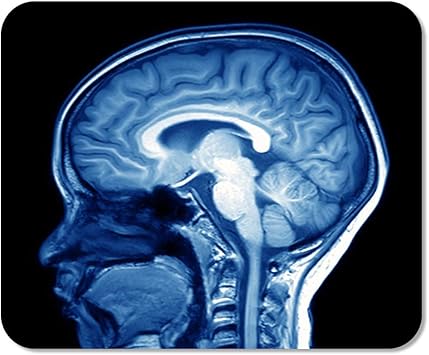

Scanner cerveau. Scanner m du cerveau liver scan échographie f du foie American English Would you like to translate a full sentence?. During the scan you will lie on a platform which slides into the scanner (a bit like going into a tunnel) It is important to lie still during the scan so that the machine can take clear pictures of your brain An MRI scan is usually a series of short scans with breaks in between, rather than one long scan. Le scanner permet par exemple de suivre l'évolution d'une hémorragie, d'une tumeur L’IRM mieux voir les organes, notamment le cerveau L' IRM (imagerie à résonance magnétique).

During the scan you will lie on a platform which slides into the scanner (a bit like going into a tunnel) It is important to lie still during the scan so that the machine can take clear pictures of your brain An MRI scan is usually a series of short scans with breaks in between, rather than one long scan. BOSTON(BUSINESS WIRE)May 4, Cerveau Technologies Inc today announced a research collaboration with University College London (UCL), a leading UK academic center for the production and application of imaging biomarkers for use in clinical research, that grants the institution the right to manufacture 18 FMK6240, a next generation investigational Positron Emission Tomography (PET. Scan (skăn) v scanned, scan·ning, scans vtr 1 a To look at carefully or thoroughly, especially in search of something;.

During the scan you will lie on a platform which slides into the scanner (a bit like going into a tunnel) It is important to lie still during the scan so that the machine can take clear pictures of your brain An MRI scan is usually a series of short scans with breaks in between, rather than one long scan. Neuromarketing scanner le cerveau un reportage de Canal Jimmy Genaro Jace Follow 6 years ago 47 views Neuromarketing scanner le cerveau un reportage de Canal Jimmy Report Browse more videos Playing next Cash investigation Neuromarketing votre cerveau les intéresse / intégrale. Et pour le coup je crois que si l'on scannait le cerveau de notre docteur en herbe, on y découvrirait de vastes zones de bêtise à l'état pur et très inquiétante pour notre système.

L'appareil d'IRM a fait un scanner du cerveau de Léo mais n'a pas trouvé de tumeurs scan n noun Refers to person, place, thing, quality, etc (medical test by machine) ( Médecine, courant ). FOUNDING PARTNERS SUPPORTING PARTNERS Disclaimer;. “Cerveau welcomes this opportunity to continue working with the KU Leuven researchers to understand the application of MK6240 and how it may benefit patients with brain diseases.